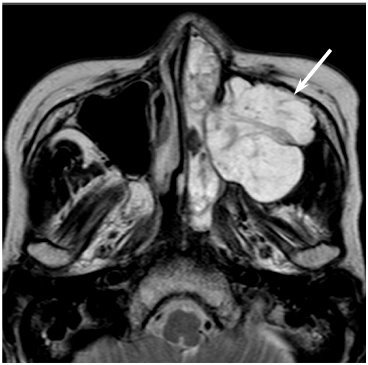

Para el descarte de esta enfermedad, se requerirá de un examen físico por parte del médico especialista en cabeza y cuello, a veces una exploración endoscópica llamada “nasolaringoscopía” o estudio de imágenes como la tomografía o resonancia magnética, además de una biopsia de ser necesaria que confirmaría el diagnóstico oncológico. Una vez realizadas todas las evaluaciones y hecho el diagnóstico, se propondrá el tratamiento correspondiente, que puede ser realizado con cirugía principalmente, radioterapia, quimioterapia, inmunoterapia o alguna combinación de las anteriores.